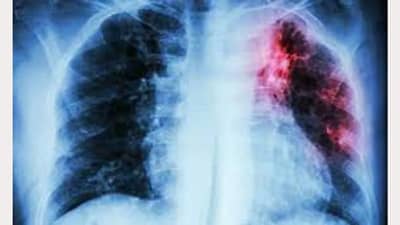

તેમણે જણાવ્યું કે દરેક વ્યક્તિમાં માયકોબેક્ટેરિયમ ટ્યુબરક્યુલોસિસ નામના સૂક્ષ્મ બેક્ટેરિયા હોય છે. “બેક્ટેરિયા ક્યારેય મરતા નથી પરંતુ દરેકને ચેપ લાગતા નથી.” સેન્ટર્સ ફોર ડિસીઝ કંટ્રોલ એન્ડ પ્રિવેન્શન મુજબ, બેક્ટેરિયા સામાન્ય રીતે ફેફસાં પર હુમલો કરે છે, પરંતુ ટીબીના બેક્ટેરિયા શરીરના કોઈપણ અંગ જેમ કે કિડની, કરોડરજ્જુ અને મગજ પર હુમલો કરી શકે છે. ટીબીના બેક્ટેરિયાથી સંક્રમિત દરેક વ્યક્તિ બીમાર પડતા નથી.